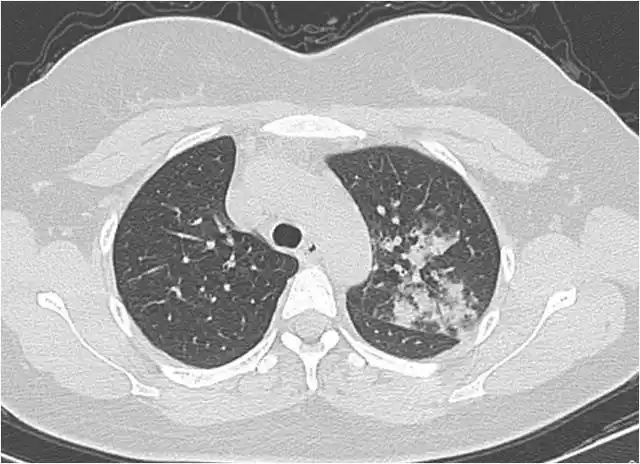

胸部ct双肺继发性肺结核,右上肺空洞形成.

粟粒型肺结核